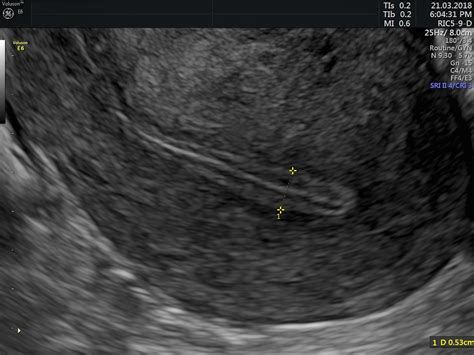

The endometrium is the inner layer of the uterus that undergoes rhythmic changes throughout the menstrual cycle. Under the influence of estrogen, this lining thickens to prepare for a potential pregnancy. If fertilization does not occur, the lining is shed during menstruation. For an embryo to successfully implant, the lining generally needs to reach a specific thickness, typically measured via transvaginal ultrasound.

• Receptivity: Thickness alone is not the only factor; the trilaminar appearance (a triple-stripe pattern seen on ultrasound) is also crucial for confirming the lining is receptive to an embryo.

1. Transvaginal Ultrasound: The standard tool for monitoring the endometrial cycle in real-time.